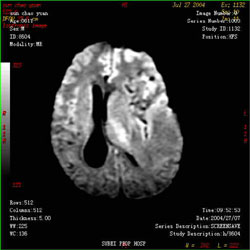

額葉腫瘤CT圖1)前後位像:前後位像上大腦前動脈水平段和上行段近側向外上明顯移位,呈凹弧形抬高此弧形輪廓可示腫瘤的上界。因前動脈垂直段下部已向外上移位,故見其相對上移和縮短腫瘤偏於一側者,向對側位較明顯;位於中線或累及兩側者,可無中線移位或移位較輕微。

2)側位像:頸內動脈床突上段向下向後移位,使虹吸彎受壓變扁。頸內動脈分支向後移位腫瘤靠近中線,則前動脈垂直段及膝段牽直,向後上移位。腦外腫瘤多呈弧形,可描繪出腫瘤輪廓。腫瘤偏外,則前動脈無上述變化,可使中動脈側裂段向下移位,額頂升動脈牽直且向後下方移位。腫瘤居中線或累及兩側,可影響兩側頸內動脈及大腦前動脈。

3)靜脈期:可見視丘紋狀靜脈和隔靜脈牽直並向上後方移位。大腦內靜脈前段向後上移位且彎曲度增大,靜脈角亦向上移位。這些改變的出現與腫瘤大小有關。